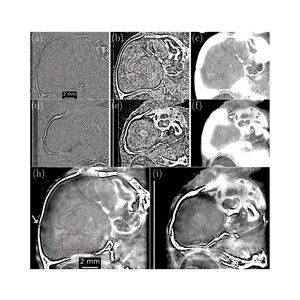

The September issue of @jsynchrotronrad.iucr.org is now online bit.ly/3UUlj8b The cover shows source property characterization of the upgraded Advanced Photon Source using grating interferometry bit.ly/3JIgexq